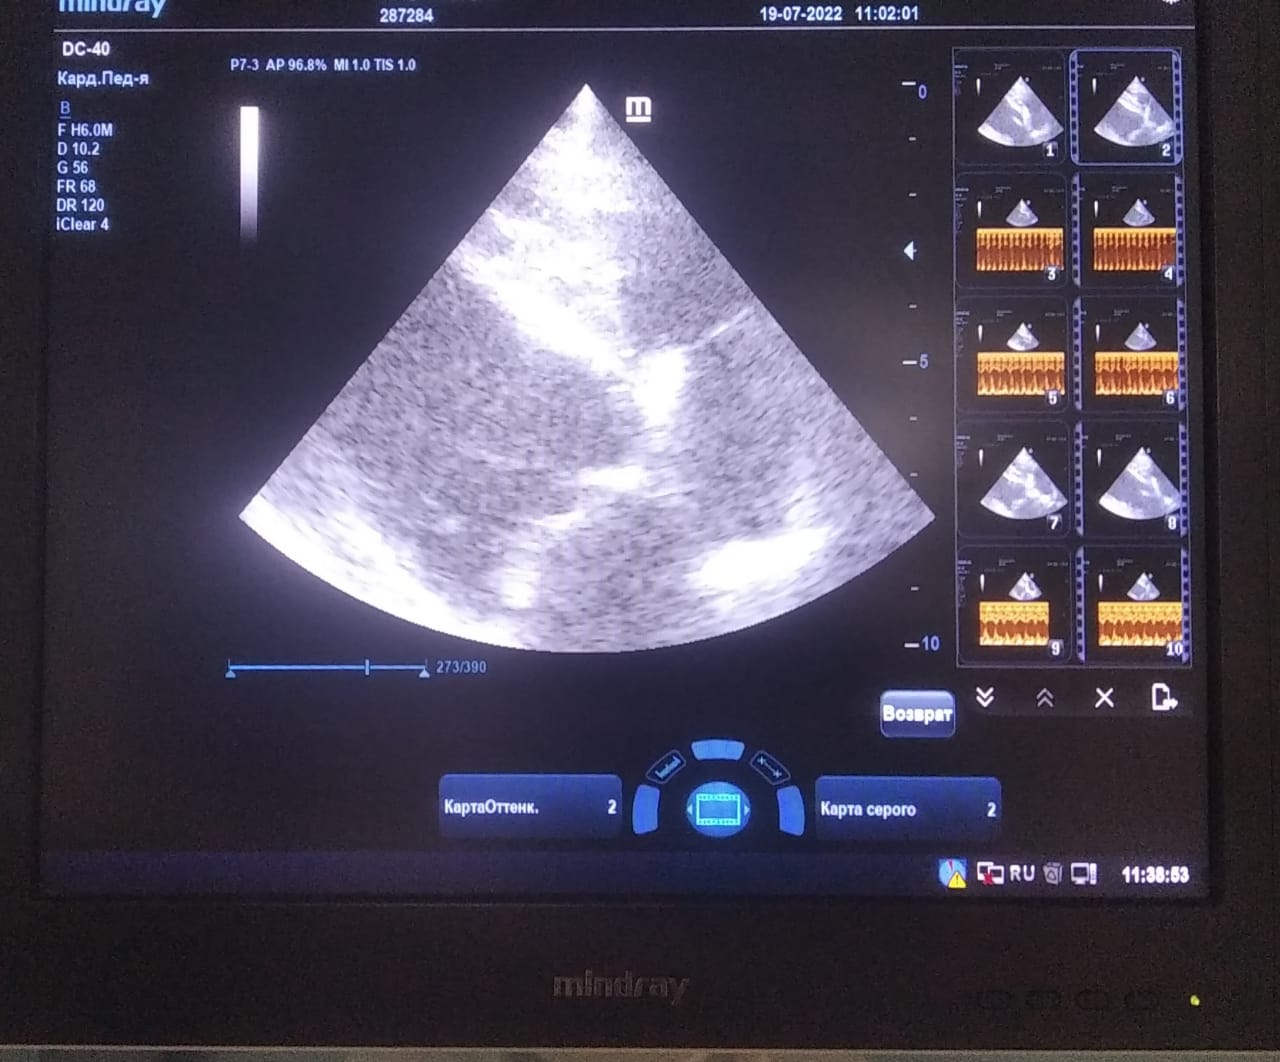

Анализы Арчи. Сердца и легких

Вложения

IMG-20220719-WA0100.jpg

IMG-20220719-WA0102.jpg

IMG-20220719-WA0104.jpg

IMG-20220719-WA0103.jpg

IMG-20220719-WA0105.jpg

Продолжение.

IMG-20220719-WA0097.jpg

IMG-20220719-WA0096.jpg

IMG-20220719-WA0099.jpg

IMG-20220719-WA0098.jpg

IMG-20220719-WA0101.jpg

Еще

IMG-20220719-WA0091.jpg

IMG-20220719-WA0092.jpg

IMG-20220719-WA0093.jpg

IMG-20220719-WA0094.jpg

IMG-20220719-WA0095.jpg

IMG-20220719-WA0052.jpg

IMG-20220719-WA0054.jpg

IMG-20220719-WA0055.jpg

IMG-20220719-WA0090.jpg

IMG-20220719-WA0089.jpg

И чуток

IMG-20220719-WA0053.jpg